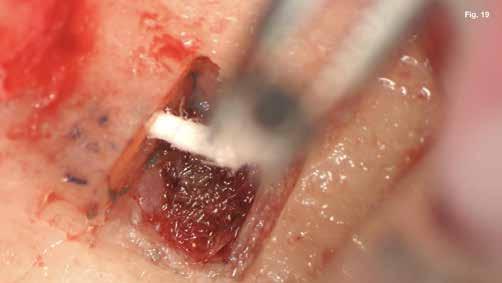

A szubmarginális teljes vastagságú lebenyt két felszabadító bemetszéssel végeztük egy 69-es számú, dupla lekerekített mikropengével (Swann–Morton) (6–7. ábra) A vestibularis csont ép volt, ezért csontablak-technikát alkalmaztunk és végeztünk (6–8. ábra) piezo készülékkel (Woodpecker DTE AI Surgery) és „US1, UC1” (Guilin Woodpecker Medical Instrument Co., LTD) hegyekkel. A blokkot az intraoperatív szakaszok alatt sóoldatban tartot-

tuk. Az apikális reszekciót (8. ábra) az „UC1” (Guilin Woodpecker Medical Instrument Co., LTD) segítségével végeztük el, és a gyökeret egy 3 mm-es „MM4” (Hu-Friedy Manufacturing Co. LLC) kerek tükörrel vizsgáltuk a VRF szempontjából (13. ábra). A gyökérvég polírozását (11. ábra) az „UL4” (Guilin Woodpecker Medical Instrument Co., LTD) segítségével végeztük. A csontos kripta küretizálása kézi küretezéssel történt, de a csontos kriptában lévő további hámbélés eltávolításával a gyógyulási folyamat felgyorsítása érdekében piezo „UL3” (Guilin Woodpecker Medical Instrument Co., LTD) piezo hegyet is használtunk (9–10. ábra). A három mm-es retropreparációt (14–17. ábra) a „JT2SA” hegy (B&L Biotech) segítségével végeztük el. A retropreparációt ismét ellenőriztük a guttapercha maradványok tekintetében, leöblítettük és papírhegyekkel meg-